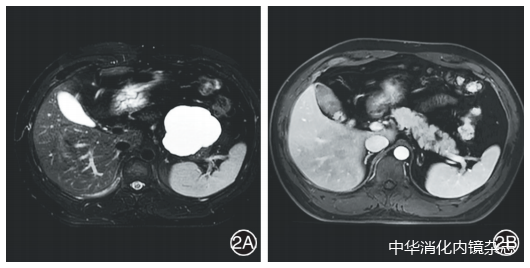

图2内镜超声引导下聚桂醇消融术后病变完全缓解2A:消融前MRI显示胰尾部71.0 mm×68.0 mm囊性肿瘤;2B:消融后4个月复查MRI,病变缩小至12.0 mm×7.0 mm